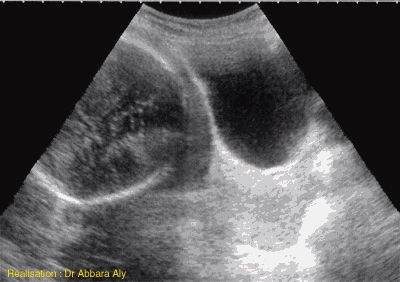

Coupe sagittale passant par le col utérin

et le segment inférieur à 36 SA